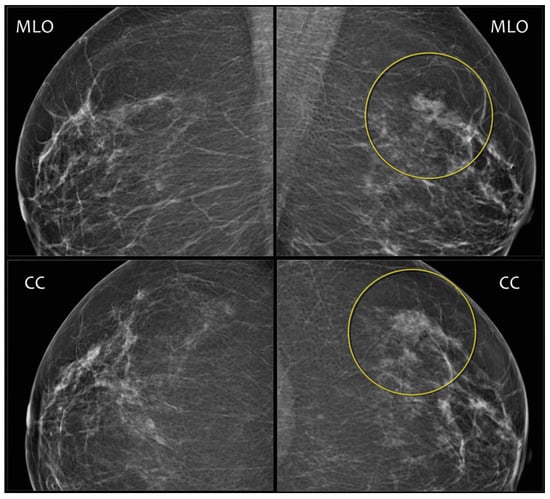

2. Mammography Assessment Process

Mammography databases can offer various types of information. To better understand this information, it is valuable to understand the image examination process of a radiologist. The standard mammographic examination consists of four images, two projections for each breast: the craniocaudal (CC) view, which is a top-to-bottom view, and the mediolateral oblique (MLO) view, which is an oblique view (Figure 1). The ACR BI-RADS Atlas 2013 [10] was designed to standardize breast imaging reporting (Figure 2).

Figure 1. Four standard views: (a) right CC, (b) left CC, (c) right MLO, (d) left MLO. Source: [11].